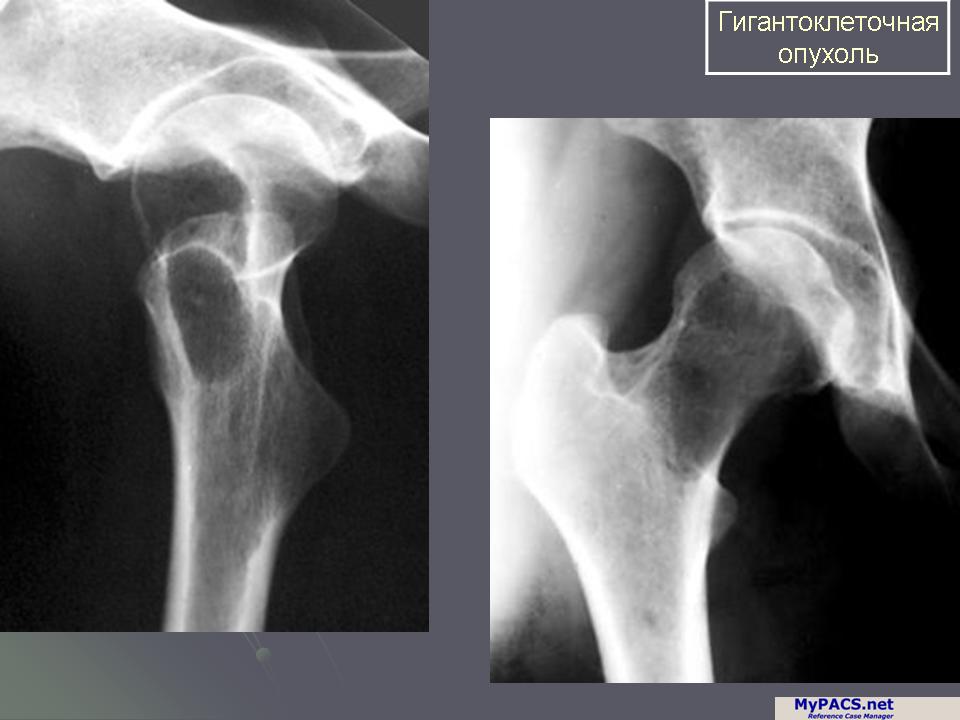

Рентгеновские снимки саркомы плечевого сустава